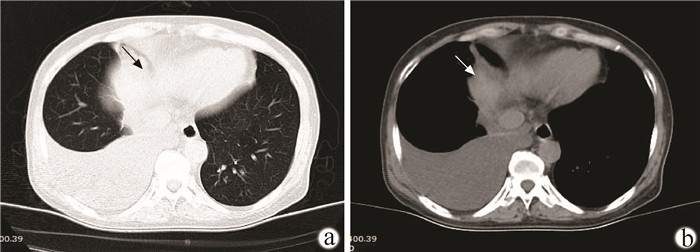

肝性胸水临床研究进展与挑战

马博, 尚天玲, 黄剑洁, 涂芷馨, 王妍, 韩雨金, 温晓玉, 金清龙

2022, 38(2): 452-456. DOI: 10.3969/j.issn.1001-5256.2022.02.040

摘要(1540) HTML (493) PDF (1934KB)(125)

摘要:

肝性胸水(HH)是肝硬化与门静脉高压相关的一种极具挑战性的并发症,其发生机制及治疗措施仍不完全明确。总结评述了HH的发病机制、临床表现、诊断治疗等方面最新研究进展与挑战,并提供一个多学科的治疗策略,包括减少腹水的产生、防止积液进入胸腔、胸腔积液清除、胸膜腔闭塞和肝移植5部分,以期为更多临床医生提供参考。